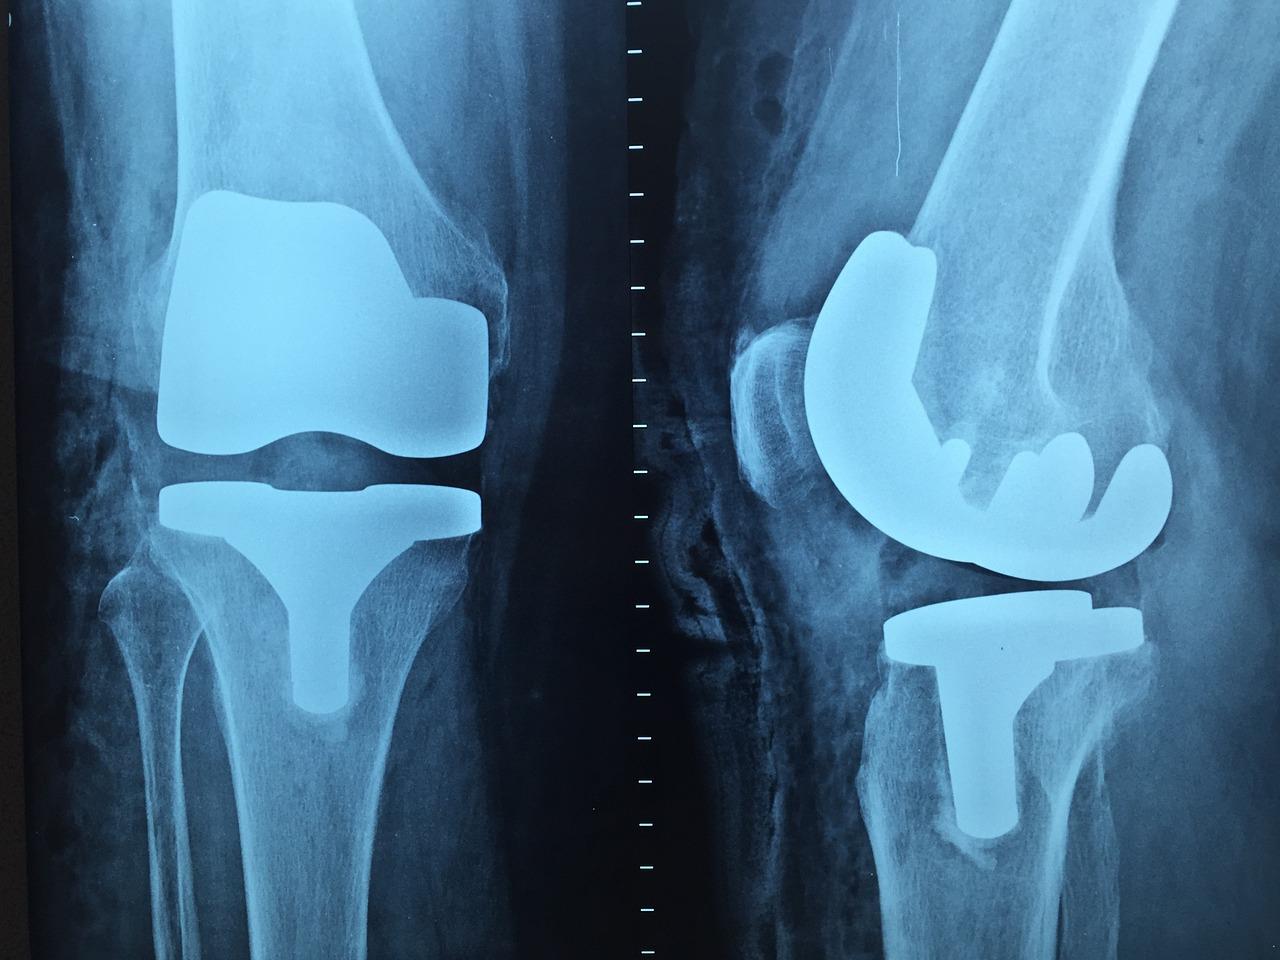

De orthopedische chirurgen in Heerhugowaard zijn vaak gespecialiseerd in specifieke gebieden van de orthopedie, zoals gewrichtsvervangingen, sportgeneeskunde, traumatologie, kinderorthopedie of rugchirurgie. Deze specialisaties stellen hen in staat om diepgaande kennis en expertise te ontwikkelen op hun vakgebied, waardoor ze in staat zijn om complexe gevallen effectief te behandelen en optimale resultaten te behalen voor hun patiënten.

De orthopedie in Heerhugowaard maakt gebruik van geavanceerde technologieën en innovatieve benaderingen om de diagnose, behandeling en revalidatie van orthopedische aandoeningen te verbeteren. Deze technologieën variëren van geavanceerde beeldvormingstechnieken en robotica tot minimaal invasieve chirurgische procedures en op maat gemaakte prothesen en implantaten.

Door gebruik te maken van deze cutting-edge technologieën kunnen orthopedische specialisten in Heerhugowaard nauwkeurigere diagnoses stellen, meer gepersonaliseerde behandelplannen opstellen en betere resultaten behalen voor hun patiënten. Dit kan leiden tot kortere hersteltijden, verminderde complicaties en verbeterde langetermijnresultaten voor patiënten met orthopedische aandoeningen.

De orthopedische zorg in Heerhugowaard wordt voortdurend verbeterd door de integratie van innovatieve technologieën en geavanceerde apparatuur die zijn ontworpen om de nauwkeurigheid, efficiëntie en veiligheid van orthopedische procedures te verbeteren. Deze technologieën variëren van geavanceerde beeldvormingssystemen en robotgestuurde chirurgische platforms tot 3D-printing van op maat gemaakte implantaten en protheses.

Door gebruik te maken van deze geavanceerde technologieën kunnen orthopedische chirurgen in Heerhugowaard nauwkeuriger en minder invasieve procedures uitvoeren, waardoor de hersteltijd van de patiënt wordt verkort en de kans op complicaties wordt verminderd. Bovendien kunnen op maat gemaakte implantaten en protheses een betere pasvorm en functionaliteit bieden, wat resulteert in een verbeterde kwaliteit van leven voor de patiënt.